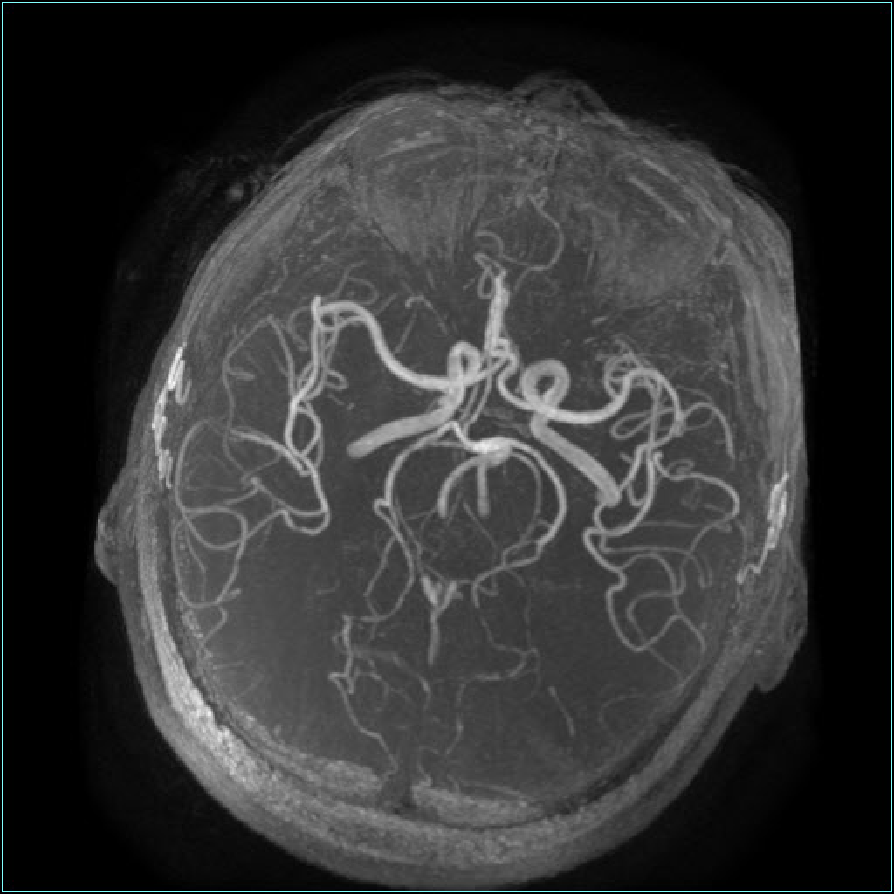

入院后行头颅磁共振示:1.中脑、双侧丘脑梗死;2.双侧脑实质多发缺血灶、软化灶;3.MRA示双侧大脑后动脉硬化样表现。

(图2.头颅MRA示双侧大脑后动脉粥样硬化)